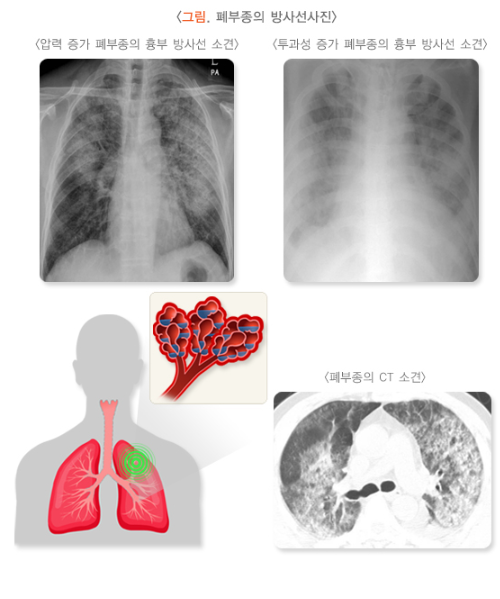

4. 영상 검사 (Imaging Studies)

- 흉부 X-ray(Chest X-ray):

- 흉부 X-ray는 가장 기초적인 검사로, 폐에 대한 구조적 변화를 확인할 수 있습니다.

- 급성 폐부종, 폐렴, 기흉, 기계적 손상 등의 변화를 관찰할 수 있습니다.

- 흉부 X-ray에서 나타날 수 있는 소견으로는 폐에 흐려진 영역, 기침으로 인한 기침 유발 가래나 유리한 질감 등을 관찰할 수 있습니다.

- 흉부 CT(Chest CT scan):

- CT 스캔은 보다 정밀한 영상 검사로, 흉부 X-ray에서 보이지 않는 세밀한 폐 손상을 파악할 수 있습니다.

- 기계적 손상, 염증이나 조직 파괴 등을 상세하게 볼 수 있습니다.

- CT는 특히 급성 폐부종이나 기계적 폐쇄가 의심되는 경우, 미세한 폐의 이상을 더 정확히 평가하는 데 유용합니다.

흡입성 폐손상의 진단은 환자의 사고 이력과 증상을 바탕으로 영상 검사, 혈액 검사, 기능 검사 등을 통해 종합적으로 이루어집니다. 흉부 X-ray와 CT 스캔을 통한 영상 검사가 가장 중요한 진단 도구로 사용되며, 산소화 상태를 측정하기 위한 동맥혈 가스 분석도 중요한 역할을 합니다. 진단이 빠르게 이루어져야 치료가 효과적으로 진행될 수 있습니다.